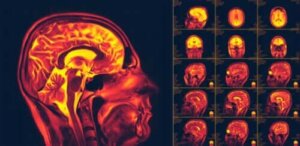

Nevroplastisitet i hjernen, også kjent som cerebral plastisitet, er en av de viktigste nyere funnene om menneskekroppen. Det er hjernens evne til å endre og tilpasse seg ny atferd eller opplevelser.

Forskere har imidlertid oppdaget at nevronene i hjernen vår kan regenereres konstant. Faktisk gjør de ikke bare dette anatomisk, de kan også skape nye koblinger. Dette konseptet er ofte kjent som “nevroplastisitet”. Selv om det virker enkelt er det dette som lar hjernen komme seg etter visse skader og lidelser.

Dermed begynte de å gjennomføre forskjellige bildebehandling- og stimuleringstester for å vise at nevroplastisitet eksisterer. Forskere undersøker fremdeles alle aspektene av dette fenomenet.